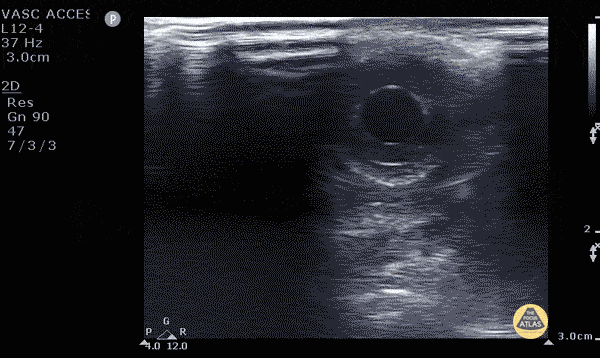

Orbital - Consensual Light Reflex

Seen is the constriction of the Pupillary Sphincter when a light is shone on the contralateral pupil, demonstrating the Consensual Pupillary Reflex. In the setting of severe Orbital trauma and swelling, POCUS may be used to assess this reflex arc. Dysfunction in the arc may be associated with pathology at the Retina, Midbrain, Optic, and/or Oculomotor nerve. Dr. Mohamed Elfatihi and Dr. Surriya Ahmad - Kings County Emergency Medicine